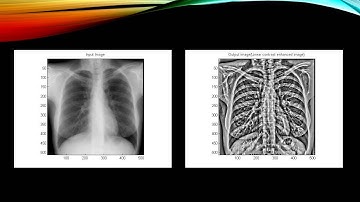

X Ray Enhancement Based on Component Attenuation, Contrast Adjustment, and Image Fusion